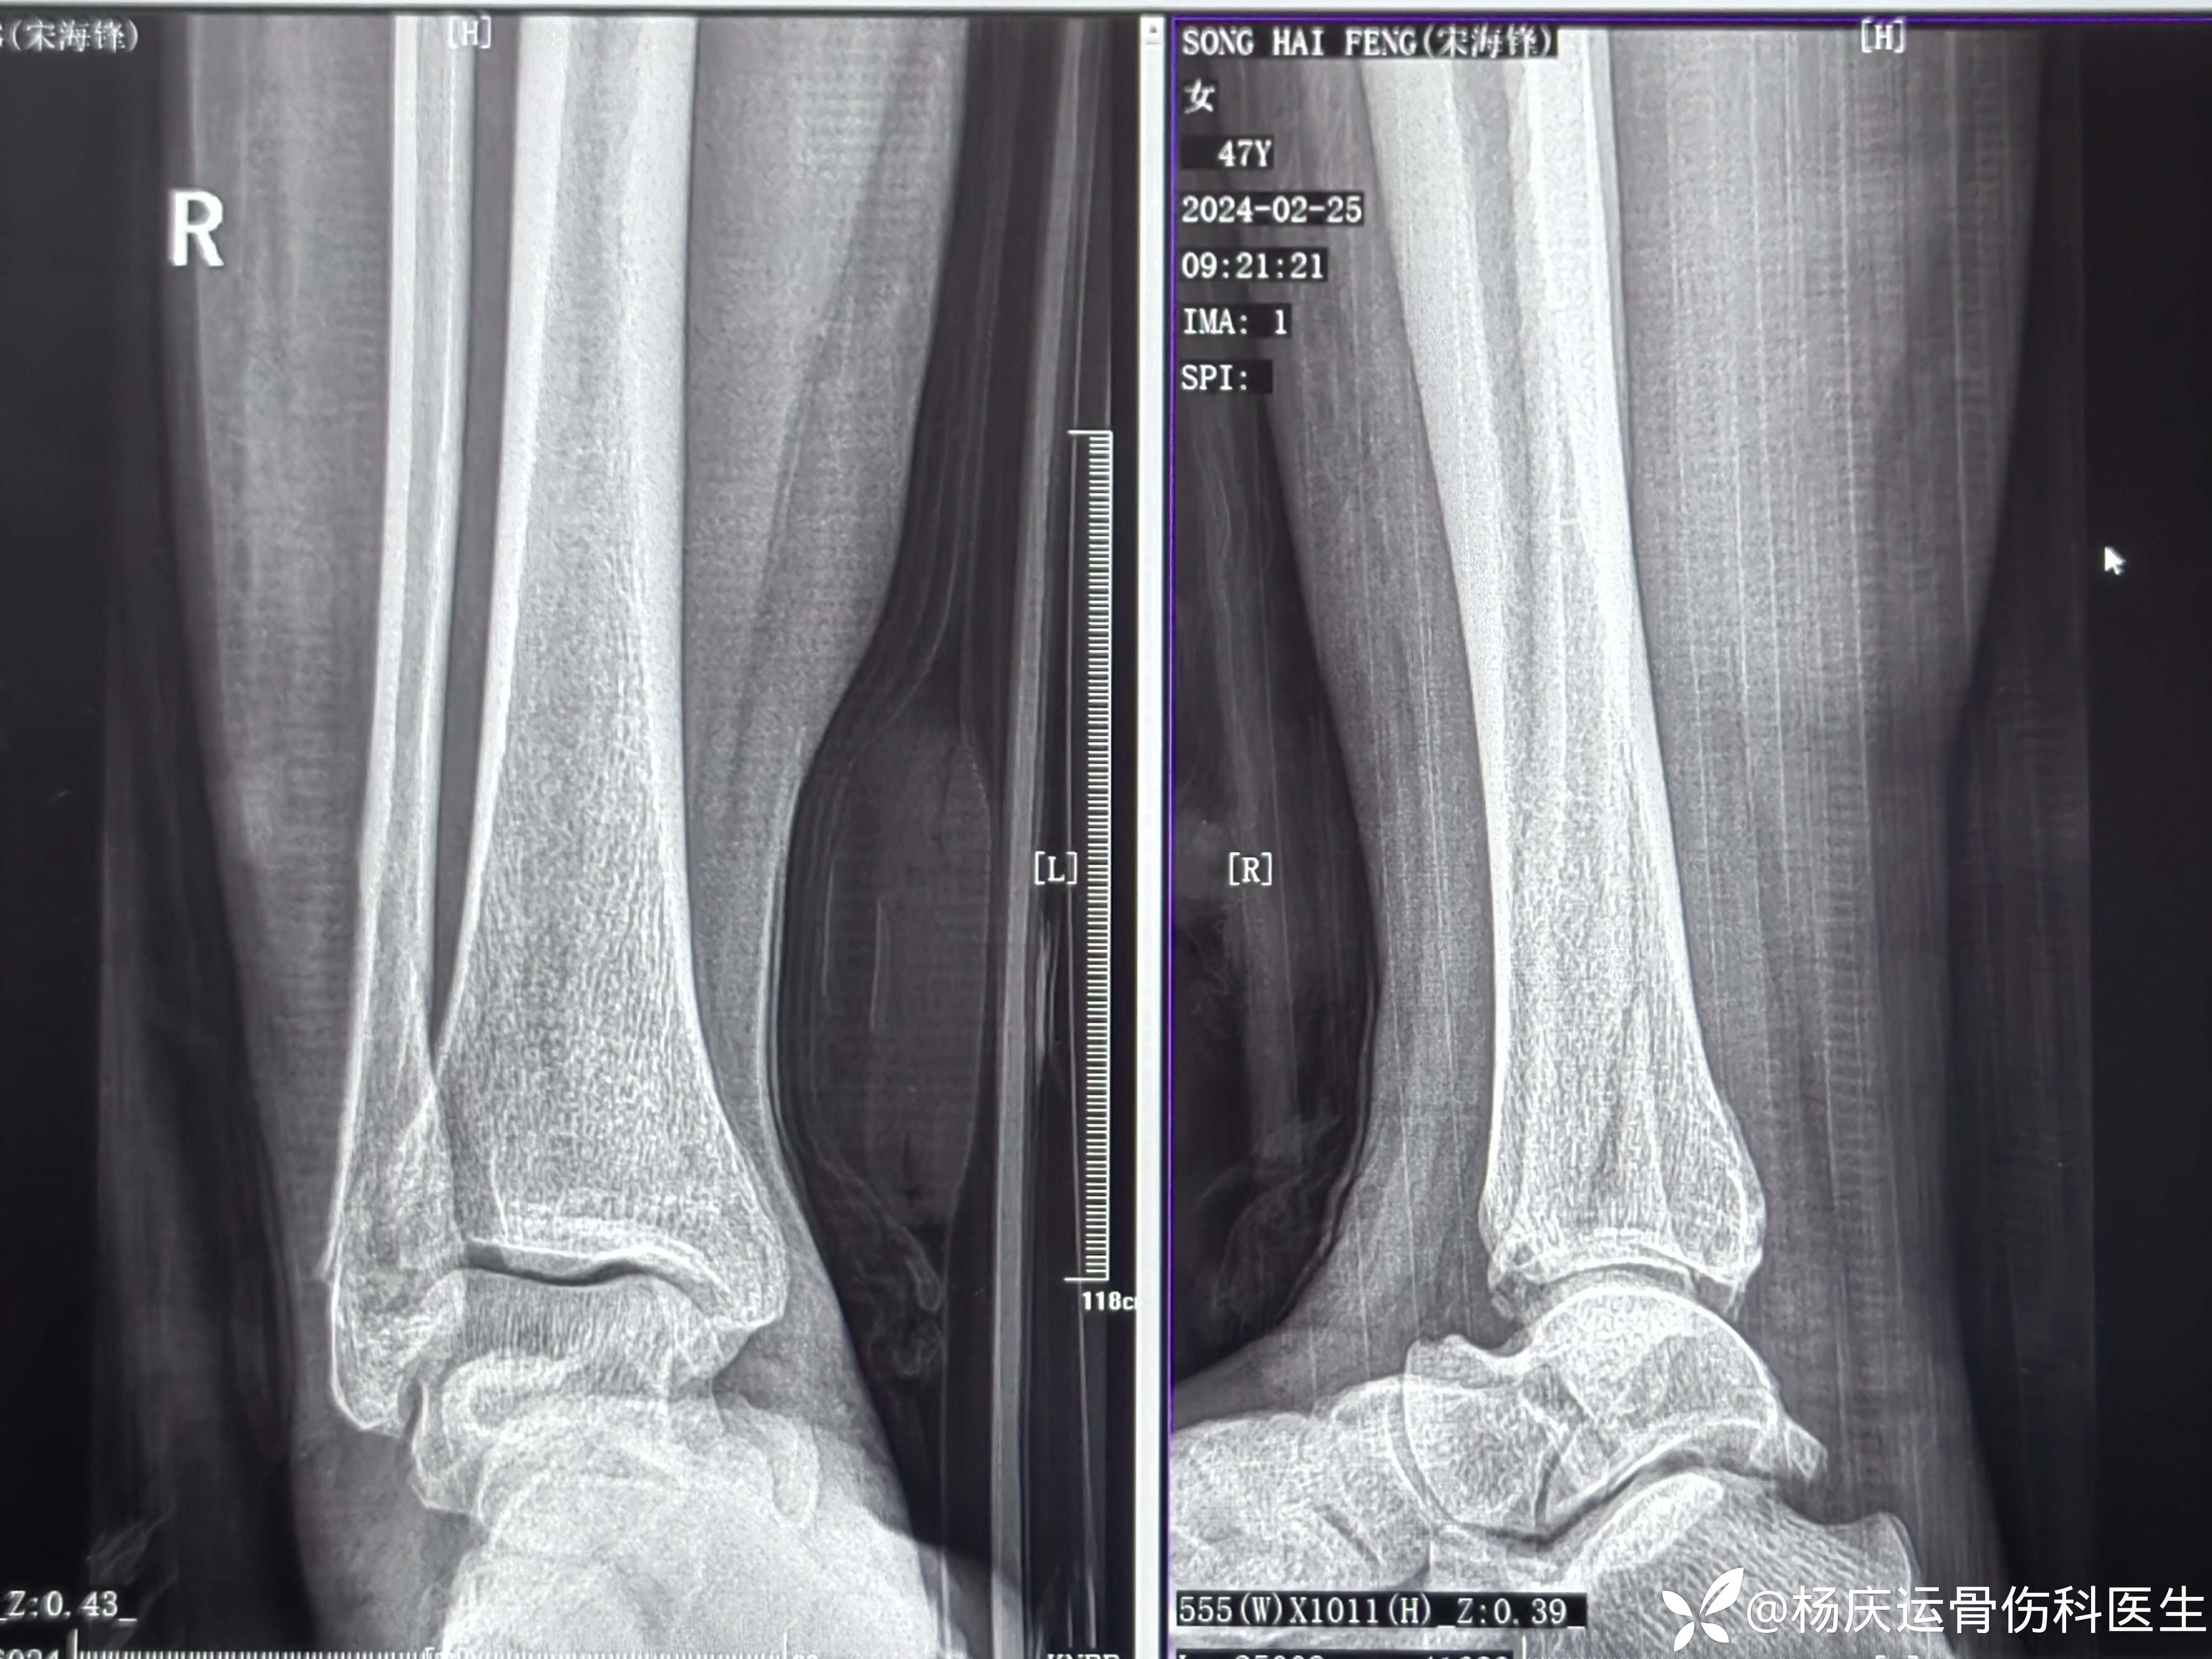

患者宋女士,47岁,右踝扭伤肿痛活动受限2小时于2024-1-30来诊。

初步诊断:右踝关节骨折

首诊三维CT

复位后